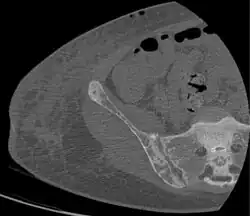

Renal osteodystrophy is usually diagnosed after treatment for end-stage kidney disease begins; however the CKD-MBD starts early in the course of CKD.[1][6] In advanced stages, blood tests will indicate decreased calcium and calcitriol (vitamin D) and increased phosphate, and parathyroid hormone levels. In earlier stages, serum calcium, phosphate levels are normal at the expense of high parathyroid hormone and fibroblast growth factor-23 levels. X-rays will also show bone features of renal osteodystrophy (subperiostic bone resorption, chondrocalcinosis at the knees and pubic symphysis, osteopenia and bone fractures) but may be difficult to differentiate from other conditions. Since the diagnosis of these bone abnormalities cannot be obtained correctly by clinical, biochemical, and imaging methods (including measurement of bone-mineral density), bone biopsy has been, and still remains, the gold standard analysis for assessing the exact type of renal osteodystrophy.[6][16]